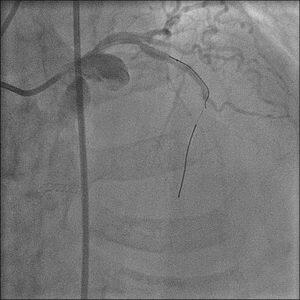

��̃P�[�X�i�ʐ^�P�C�Q�j�ŊF�Aproximal LCX total

occlusion

�Ƀ��C�A�͎h����܂���������܂���ł����B���C�A�͍ŏ���intermediate,